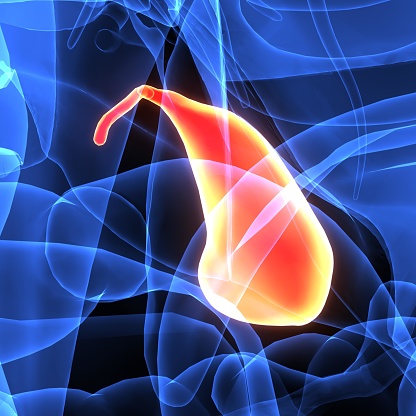

Alcoholism is an ever growing problem faced by societies throughout the world. About 86 percent of Americans over the age of 18 reported drinking at some point in their lifetime. Alcohol Awareness Month, held on April of every year, aims at increasing awareness about its causes, treatment, and recovery. This year the theme is “Changing ...click here to read more